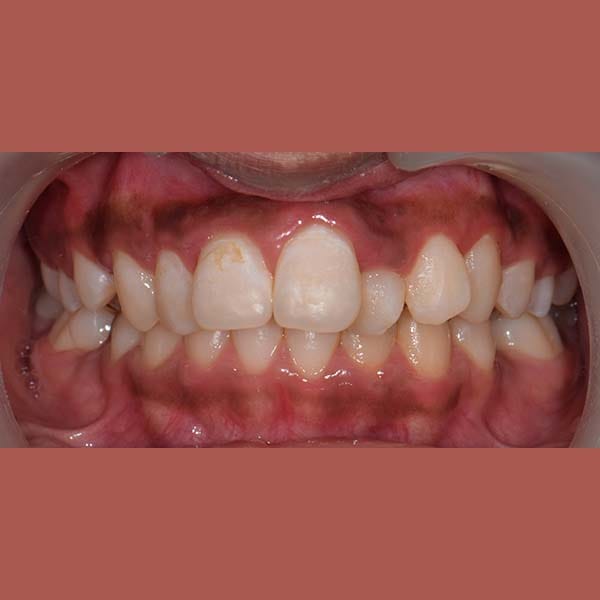

بعد

ابتسامة جميلة جدا